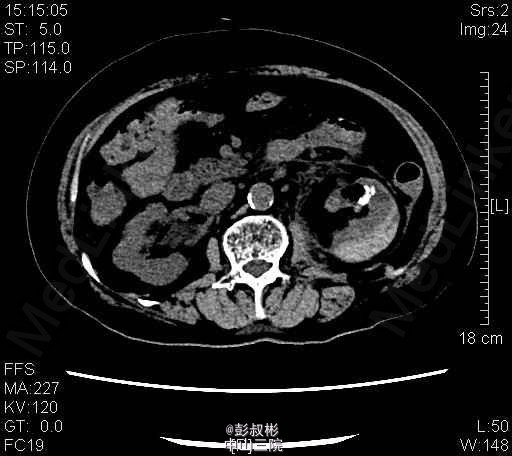

1、患者,女 80岁 2、主诉:左侧腰痛伴发热2天。 3、病史:患者于2天前无明显诱因突发左侧腰痛伴发热,畏寒,最高体温40.1℃,经急诊入院。患者曾于1年前被诊断为“双肾多发结石”,行“左侧经皮肾镜碎石取石术”后好转出院。 4、入院查体:左肾区叩击痛(+),左侧肋脊点、肋腰点压痛(+)。 5、辅助检查:KUB检查示:考虑左输尿管上段结石。B超提示:左肾积脓。胸部正位片:1、双肺纹理增粗,双下胸膜增厚。2、心影增大,主动脉硬化。 6、诊疗过程:患者于入院当晚突发高热、伴寒战、畏寒,最高体温40℃,伴恶心、呕吐,立即予抗感染等治疗。经有效治疗后患者体温有所下降。 随后患者突发抽搐,仍伴寒战、畏寒、意识模糊,予地塞米松10mg静推,加用凡拉蒙2ml肌注,非那根20mg肌注,冬眠灵12.5mg肌注后,控制仍不佳。遂行床边穿刺、抽脓。术后症状有所缓解。术后继续抗感染,患者体温恢复正常,症状明显缓解,无其他不适,遂予出院。